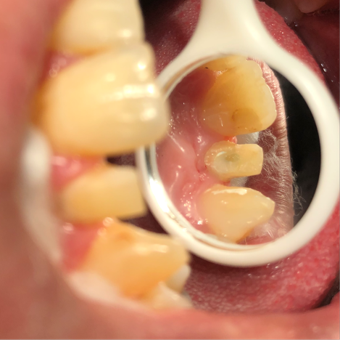

Root canal obturation

1/6/2025,post placement,tooth preparation,impression taking

1/16/2025: All-ceramic crown restoration for #12; patient asymptomatic